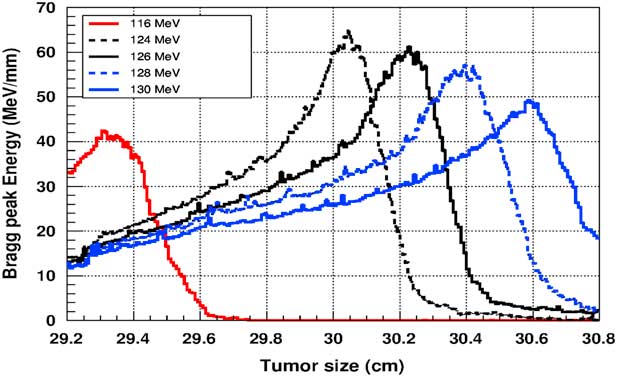

Figure 5 shows the plot of the deposited energy of a monoenergetic proton beam along the tumour size. As this figure shows, to surround completely a such tumour we should use a proton beam energy, ranging between 116 and 126 MeV. For this range energy, the Bragg peak energy is around 40 MeV and the half-value width for each Bragg peak is about 50% of the tumour size. The effect of adding gold in the tumour on the Bragg peak energy is shown in Figure 6. In this figure, we notice that the Bragg peak is localised in the tumour for the proton beam energy ranging between 116 and 130 MeV. The Bragg peak energy at the centre of the tumour is greater than without GNPs, in this case, with the presence of GNPs, the proton therapy is enhanced up to 75%, this is due to the concentration of GNPs at the centre of the tumour. Moreover, for high proton beam energy like 130 MeV, the width at half height of the Bragg peak is around of 75% of the tumour size. Comparing with previous results, the presence of GNPs in the tumour makes the width at half height of Bragg peak larger. This result shows that adding GNPs in tumours makes the proton therapy easier in clinical medicine and presents more benefit. Similarly in Figure 7, we plotted the deposited energy in the tumour with the presence of nanoplatinum materials. In this figure, the Bragg peak is localised in the tumour for the proton beam energy ranging between 116 and 132 MeV. Comparing with previous results, the width at half height of the Bragg peak is spread over 85% of the tumour. Moreover, the deposited energy at the centre in the tumour is almost double comparing with the same results in Figure 6. In the case of the use of silver NPs during this therapy, the plot of the deposited energy has the same shape as in the case of the use of GNPs (see Figure 8).

Figure 5 The deposited energy of a monoenergetic proton beam into a spherical tumour with a diameter of 1·5 cm. Notes: The proton beam energy is ranging between 116 and 126 MeV.